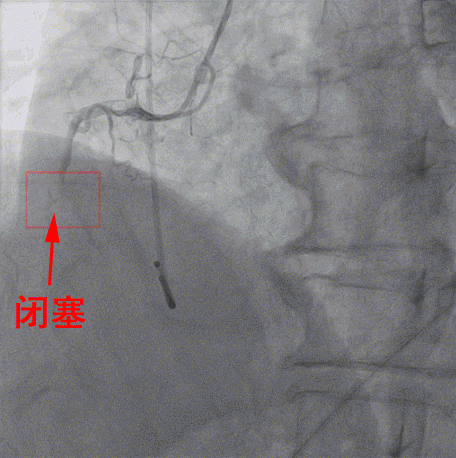

随後患者被迅速送進介入手術室,行右冠狀動脈支架手術,手術由内一科(心内)馬澤洪醫生等實施。經DSA引導下冠狀動脈造影顯示,患者右冠狀動脈近端完全閉塞,意味着右冠脈無法供血給心肌,心肌大面積處于嚴重缺血、缺氧的瀕死狀态。

△介入手術進行中